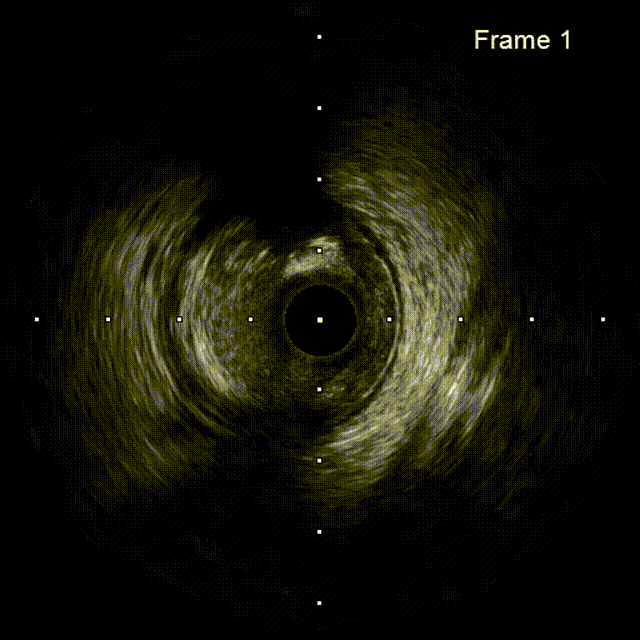

ROTA后评估

IVUS可见RCA近中段弥漫钙化病变,多>270°钙化环,3# 近端钙化壁较厚,可见旋磨后多重反射影;近中段病变扩张不充分,钙化环未见明显断裂,IVUS导管未能通过远端病变处。

IVUS无法通过远段

ROTA后评估远段

IVUS结果:远端钙化处可见360°钙化环断裂,多重反射影;远端血管直径约2.5mm。

再次IVUS评估

IVUS结果:可见近段及中段多处钙化环断裂,管腔狭窄明显改善;远端钙化环较厚未见明显断裂,管腔扩张不充分。

前后IVUS对比